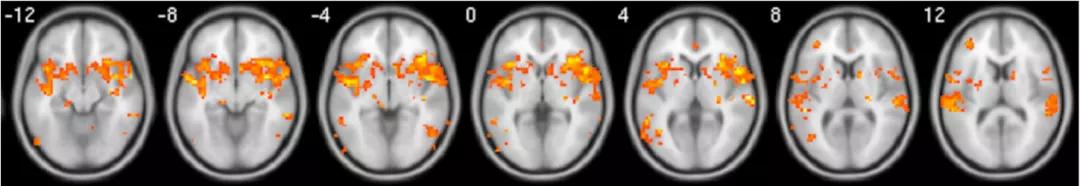

2018年,一篇发表在Bioimpacts杂志上的论文通过核磁共振成像技术展示了 人们在观看ASMR视频时的大脑变化。

实验招募了10名对ASMR敏感的被试,并邀请他们观看ASMR视频,视频内容包括 耳语、轻拍、抚摸头发 等。

实验过程中,被试被要求根据自己当下的感觉选择性地摁下按钮:

当感觉从头部和颈部产生了舒服的酥麻之感时,就摁下酥麻(tingle)按钮;

如果并没有酥麻的感觉但是觉得非常轻松、愉悦,类似于发呆状态,就摁下放松(relaxation)按钮;

要是即没有放松,也没有酥麻的感觉,就摁住基线(baseline)按钮。

同时,实验者对他们的脑电变化进行了全程监测。

实验结束后,实验者把酥麻状态下与基线状态下的脑电反应进行了对比。

他们发现,在酥麻状态下,被试的前扣带皮层、脑岛、伏隔核都被激活了,要知道这几个脑区都是大脑中负责 奖赏 的区域!

它们的激活说明ASMR使大脑感觉被奖励,从而产生了快乐的情绪,获得酥麻、愉悦的奇妙体验。